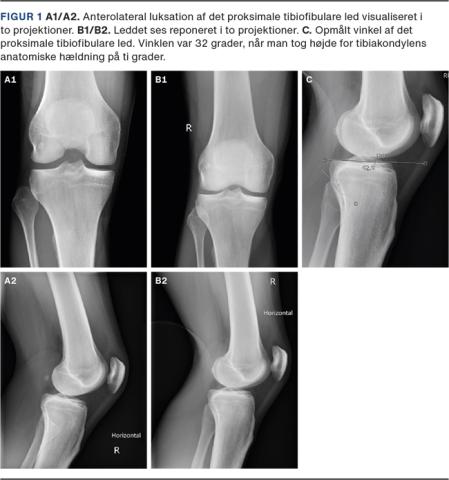

En røntgenoptagelse gav mistanke om anterolateral luksation af caput fibula (Figur 1A), hvilket blev verificeret ved røntgenoptagelse af det raske knæ.

Der blev foretaget ukompliceret lukket reposition: Knæet blev flekteret 90 grader, hvorefter foden blev udadroteret og dorsiflekteret samtidig med, at der blev lagt et direkte tryk på caput fibula fortil. En kontrolrøntgenoptagelse viste, at caput fibula var på plads (Figur 1B).

En risikofaktor for luksation af caput fibula er et skråt forløbende PTFL. PTFL er enten horisontalt eller skråt forløbende. Et skråt forløbende led defineres ved en hældning på > 20 grader [3]. Hos patienten i sygehistorien blev der udmålt en hældning på 32 grader (Figur 1C).